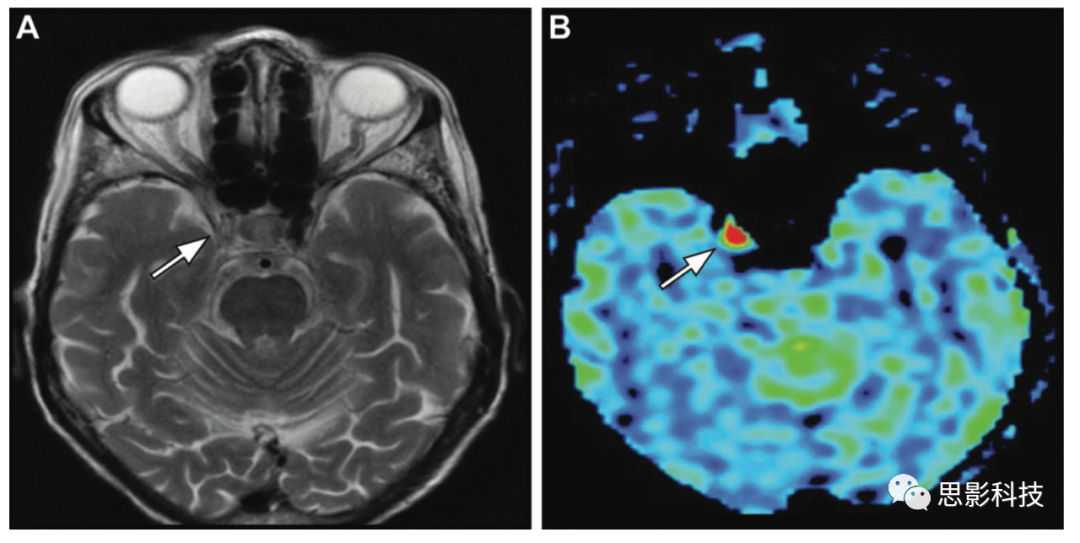

一位54歲患者因嚴(yán)重狹窄導(dǎo)致動(dòng)脈傳輸偽影。(A)右側(cè)頸內(nèi)動(dòng)脈常規(guī)血流空隙消失(箭頭)。(B)ASL MRI顯示動(dòng)脈傳輸偽影(箭頭)導(dǎo)致相應(yīng)的信號(hào)強(qiáng)度增加。